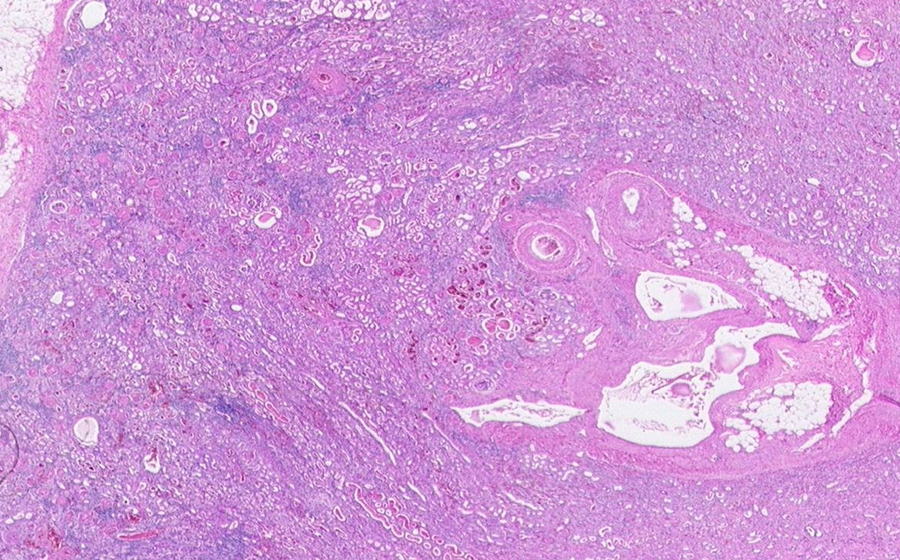

Slide 3: Glomerulonephritis - chronic

Histologic section of kidney from a patient with chronic glomerulonephritis. (click here to review normal tissue)

Image 1 - 6.3X

Slide 3 - Image 1